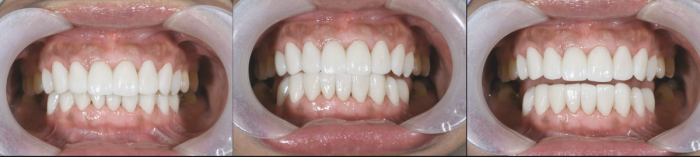

After the restorations, a beneficial intraoral functionality was observed.

21695f7c-3001-97d1-51a3-ddc12c1954c9_副本.png